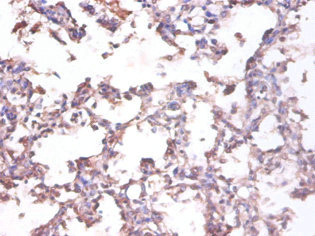

Immunohistochemistry of paraffin-embedded human lung tissue using CSB-PA07475A0Rb at dilution of 1:100